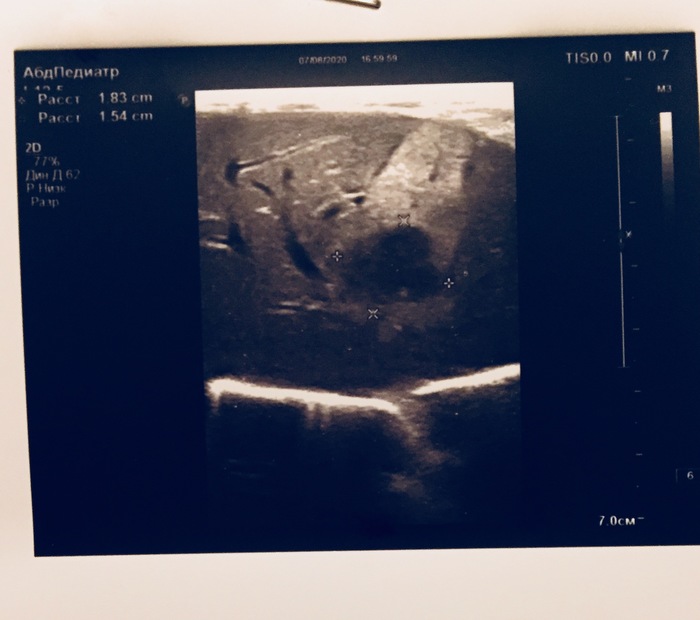

Пол года назад умерла тёща от рака молочной железы. Недавно с супругой ездили на дальняк (1000 км туда-обратно), она была за рулем. После долгой дороги у неё заболела подмышка. Прошло 3 месяца после этой поездки, боль не прошла. Сходила на УЗИ, нашли вроде как уплотнение в груди. Сказали ехать к мамологу. Супруга после этого УЗИ ходит сама не своя и плачет постоянно. Ничего не говорит. Я конечно грешу на то, что после смерти её мамы она в стрессе и все такое. Пока она в душ ходила, сфоткал документы из больницы. Будут во вложении. Подскажите пожалуйста, что это такое и чего ждать и на что это похоже, потому, что она молчит и на мои вопросы не отвечает. Заранее всем спасибо!

Узи